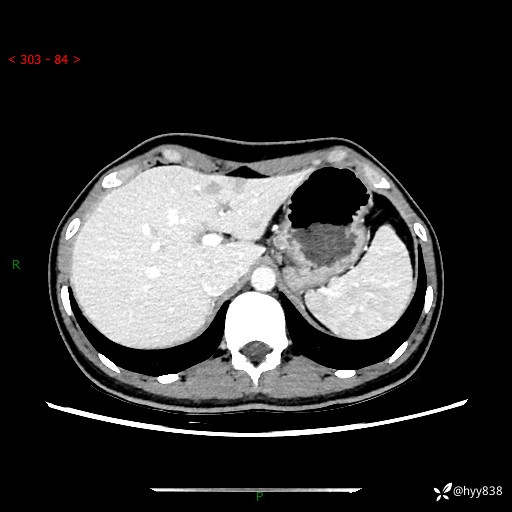

性别:女

年龄:23岁

简要病史:外院发现肝结节,来我院进一步增强确诊

上腹部CT平扫+增强

肝囊肿 (68)